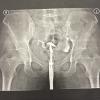

☝🙄Может кому-то понадобится, прошла ГСГ, Максимилиановская больница , переулок Пирогова , дом 2. Стоимость 7500.

Проводил заведующий отделения, врач Абесадзе Лери Георгиевич.😷💉

@a93, самочувствие после гсг в норме, живот тянуло в течении 10 минут после и все, только кровит до сих пор. Трубы проходимы✊🏼🎉 Ещё месяц подготовки к стимуляции овуляции , и приступаем 😌